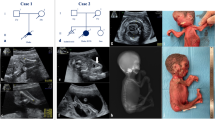

Heterozygous variants in BICD cargo adapter 2 (BICD2) cause autosomal dominant spinal muscular atrophy, lower extremity-predominant 2 (SMALED2). The disease is usually characterized by a benign or slowly progressive, congenital or early onset muscle weakness and atrophy that mainly affects the lower extremities, although some affected individuals show involvement of the arms and the shoulder girdle. Here we report unusual extremes of BICD2-related diseases: A severe form of congenital muscular atrophy with arthrogryposis multiplex, respiratory insufficiency and lethality within four months. This was caused by three BICD2 variants, (c.581A>G, p.(Gln194Arg)), (c.1626C>G, p.(Cys542Trp)) and (c.2080C>T, p.(Arg694Cys)), two of which were proven to be de novo. Affected individuals showed reduced fetal movement, weak muscle tone and sparse or no spontaneous activity after birth. Despite assisted ventilation, the condition led to early death. At the other extreme, we identified an asymptomatic woman with a known BICD2 variant (c.2108C>T, p.(Thr703Met)). Radiological examination showed fatty degeneration of selected thigh and calf muscles without clinical consequences. Instead, her son carrying the same variant is affected by a mild childhood onset disease with myopathic and neurogenic features. Mechanisms leading to variable expressivity and onset of BICD2-related disease may include alterations in molecular interactions of BICD2 and suggest the presence of genetic modifiers that may act in a protective fashion to ameliorate or abrogate disease. Our data define an additional severe disease type caused by BICD2 and emphasize a possibly variable etiology of BICD2-opathies with regard to primary muscle and neuronal involvement.